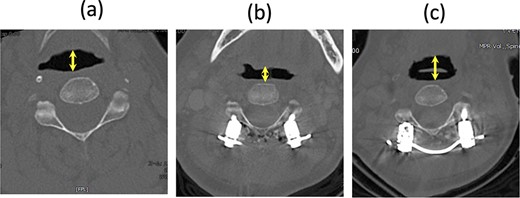

In our case, the C2–7 angle increased from −15° before the second surgery to 32° after the surgery. Considering the relationship between the O-C2 and C2–7 angles in healthy individuals, we expected the corrected O-C2 angle to be ~0°. The first potential cause of dyspnea was a significant reduction in this angle by 19° after the second surgery. Although the O-C2 angle was not fixed, if the patient’s head were retracted, for example, due to sliding down the bed with a higher pillow, the reduced O-C2 angle might have led to obstructive dyspnea, exacerbated by the patient’s delirium. The pharyngeal diameter at the C2 level on the supine CT scan decreased immediately after dyspnea and resuscitation, widening again after the final surgery (Fig. 4). A comparison of the lateral radiograph before and after the second surgery showed that the C2–7 angle increased significantly from −15° to 32°. However, standing radiographs were not taken after the second surgery and the O-C2 angle was not measured. The negative correlation between the O-C2 and C2–7 angles predicts that the O-C2 angle tends to be smaller [5, 6], even in normal standing and sitting positions (Table 1).

CT axial image at the C2 level in a supine position; (a) before the second surgery, (b) after the second surgery, and (c) after the third surgery; the arrow shows the pharyngeal diameter.